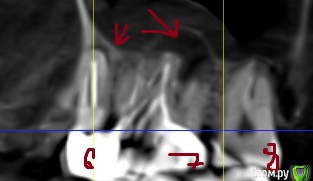

klemento Опубликовано 30 сентября, 2019 Поделиться Опубликовано 30 сентября, 2019 (изменено) Здравствуйте. Прощу помощи, т.е. совета. Проблемы слева вверху. После лечения 6 зуба и дальнейшего его протезирования вкладкой и коронкой - появилась боль при накусывании в области 5-6 зуба. Появляется преимущественно после жевания и попадания пищи. Знакомый посоветовал сделать КТ. Я обратился в 3 клиники. В 1 мне сказали удалить 6 и 7, т.к. что-то пошло в пазуху(снимок пазухи), там видно в виде пятна серого, а так же на 4 и 5 делать резекцию, т.к. выведен материал за верхушку. В двух других - сказали попытаться вскрыть 7 зуб, т.к. не понятно, что там с ним - может и получиться спасти, а 6 - не трогать(мол как простоит так простоит) . Про 5 ничего сказать не могут. Так же на 4 что-то есть и про него ничего не сказали.Хотелось бы понять как поступить. Возможно ли сохранить 7 зуб и действительно ли не трогать 6, но тогда ходить с воспалением? На одном из снимков есть двойка протезированная - на ней воспаление уже несколько лет и не беспокоит - трогать ее или делать резекцию? Понимаю, что дурак раз запустил так зубы, но обидно, что много денег отдал на 6 зуб и теперь под удаление его... Хотелось бы услышать какие-то варианты. Заранее спасибо. Изменено 30 сентября, 2019 пользователем klemento Ссылка на комментарий

krokomot Опубликовано 3 октября, 2019 Поделиться Опубликовано 3 октября, 2019 Вот КТ. Только надо вручную ссылку копировать, а то из форума не открывает.https://dropmefiles.com/1aSGrА что делать с воспалением под запротезированном зубом? Врачи снимать коронку и вкладу не хотят браться.Томограмма отвратительная, то что по ней удалось определить что в 7м не запломбирован дистальный канал, лечение перепломбировка, нужен еще прицельный снимок коронок 6-ого и 7ого, из-за наводок невозможно определить состояние тканей вокруг этих коронок и особенно в промежутке между 6-м и 7-м, в 5м выведения материала нет, в 4-м есть 0.5 мм это не критично никакие резекции делать не нужно, по поводу 2-ки лечите канал и переставляйте коронку. для обьективной картины нужна хорошая томограмма на современном томографе типа Sirona, и прицельные снимки 5-й,6-й,7-й зубы на визиографе с позиционером, а не пальцем датчик держать. Скорее всего все зубы спасабельны, но это не точно)) Ссылка на комментарий